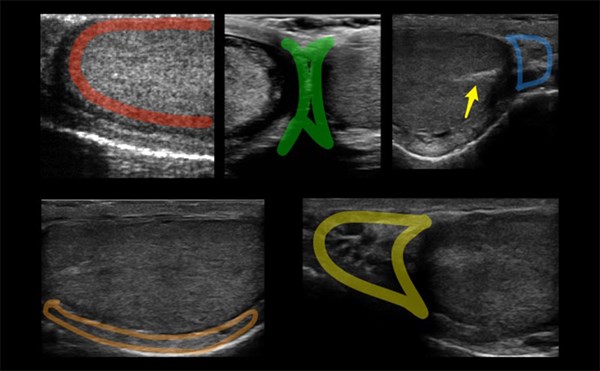

Advanced ultrasound can enhance the diagnosis of organ injury, viable tumor, and vascular pathologies at bedside.